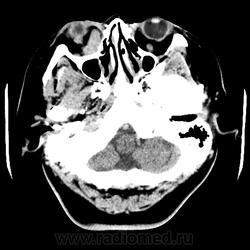

Женщина 48 лет, поступила с подозрением не ОНМК. На КТ -данных за ОНМК не обнаружено, но в правой орбите ретробульбарно мягкотканное образование +45HU, признаков деструкции и ремоделирования костных структур орбиты не наблюдается, медиальная и нижняя прямая мышца отчетливо не дифференцируются, зрительный нерв тесно прилежит к данному образованию. После КУ гомогенное накопление КВ и повышение плотности до +65HU. Экзофтальм. Жалобы на снижение зрения. Год назад делала МРТ ГМ, на снимке патологии орбит не увидел. Идиопатическая псевдоопухоль орбиты?

В мягких тканях носогубного треугольника справа тоже образование.

Натив

Контраст

На первое место все же поставила бы гемангиому. Локализация, возраст, пол, флеболит, случайная находка, безболезненный экзофтальм, ремоделирование стенок орбиты -это за гемангиому.

Кавернозная гемангиома? Ремоделирования стенок орбиты как раз таки нет, они интактны. Должна быть псевдокапсула, а здесь больше похоже на инфильтрацию прямых мышц, я за псевдоопухоль.